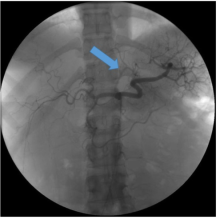

J. David Prologo, MD, FSIR, ABOM-D. Co-Investigators – Emory Interventional Radiology